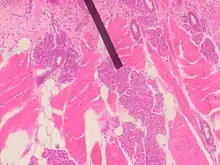

Von Ebner's glands, also called Ebner's glands or gustatory glands, are exocrine glands found in the mouth. More specifically, they are serous salivary glands which reside adjacent to the moats surrounding the circumvallate and foliate papillae just anterior to the posterior third of the tongue in its submucosa, anterior to the terminal sulcus.

Von Ebner's glands secrete lingual lipase,[1] beginning the process of lipid hydrolysis in the mouth. These glands empty their serous secretion into the base of the moats around the foliate and circumvallate papillae. This secretion presumably flushes material from the mouth to enable the taste buds to respond rapidly to changing stimuli.